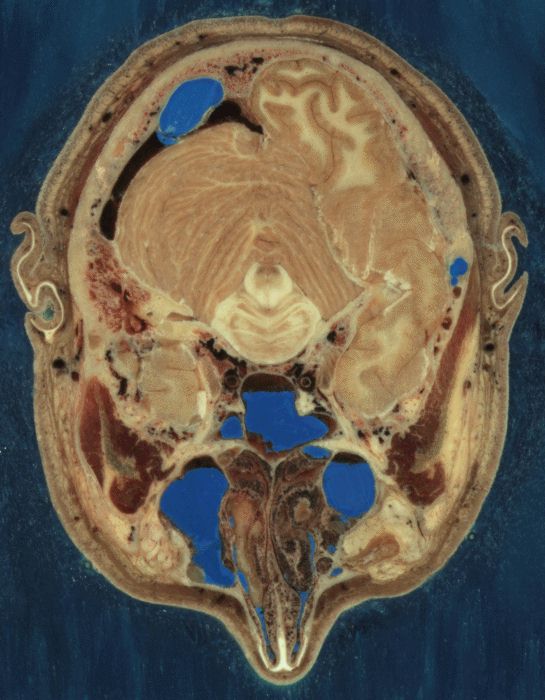

Color Cryosection

Section through Visible Human Male - head, including cerebellum, cerebral cortex, brainstem, nasal passages (from Head subset)

The Visible Human Project